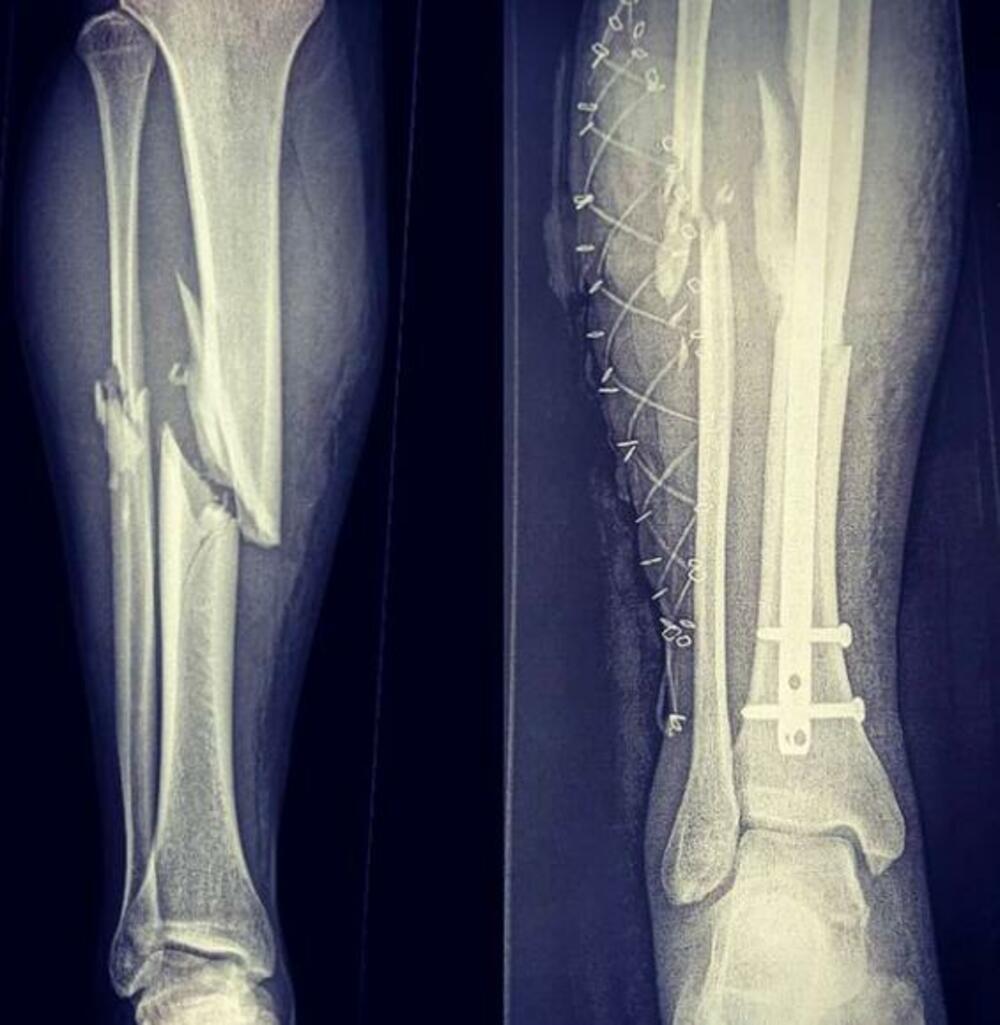

2019. godine Marko je imao nesreću zbog koje je mogao da ostane nepokretan. Lekari su mu tada rekli da bude srećan ako ponovo prohoda nakon povrede zadobijene na snegu.

Sve se desilo na treningu kada je Vukićević imao težak pad prilikom čega je polomio ruke i noge, imao unutrašnje krvarenje i oštećenje nerava. Na prvom treningu na Olimpiskim igrama bio je 52. ali svaki njegov izlazak na stazu je velika pobeda.

- Nažalost, imam operacije i tada će mi izvaditi metal iz noge koji mi drži kosti, to će biti već krajem februara da bih se spremio za sledeću sezonu, da ne bih gubio vreme. Posle Igara za mene se završava sezona, rekao je takođe Vukićević svojevremeno.